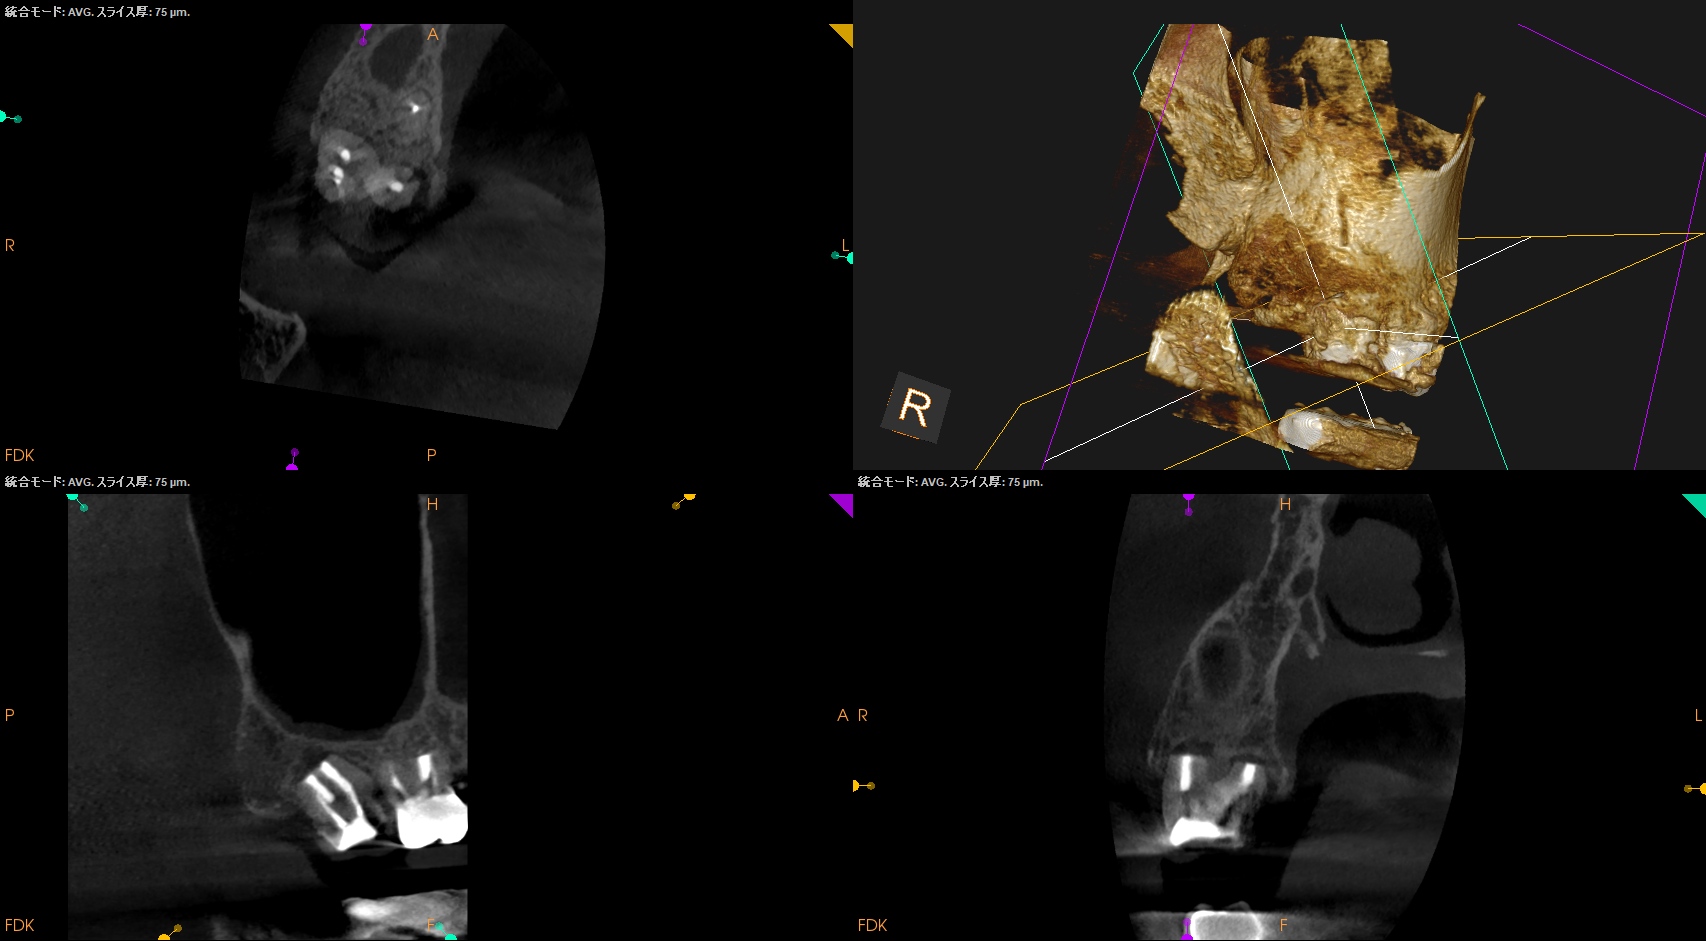

#2 Intentional Replantation 6M recall(2026.1.19)

歯牙の動揺度は生理的範囲内で歯周ポケットも深い部分がない。

最終補綴もOKだ。

術直後と比べて歯槽骨が回復し臨床症状も消失している。